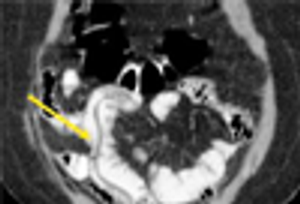

Intestinal helminthes represent one of the most prevalent types of human parasitic disease and remain a major health problem in developing countries.